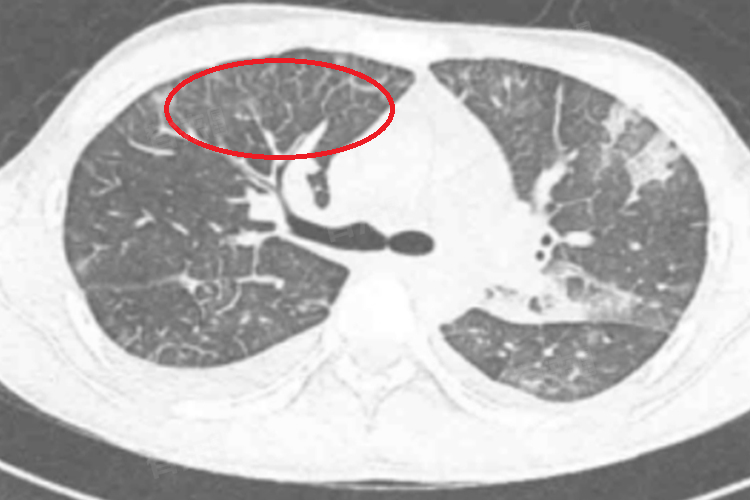

肺部磨玻璃影是指在肺部CT检查中,出现的局部密度增高影,但其边界不清,密度不足以掩盖肺纹理,类似于磨砂玻璃的外观,通常呈现为云雾状、淡薄的高密度影,可能涉及肺部的部分或全部区域。

- 影像学检查:如胸部CT、MRI等,用于观察磨玻璃影的大小、形态、位置及变化。